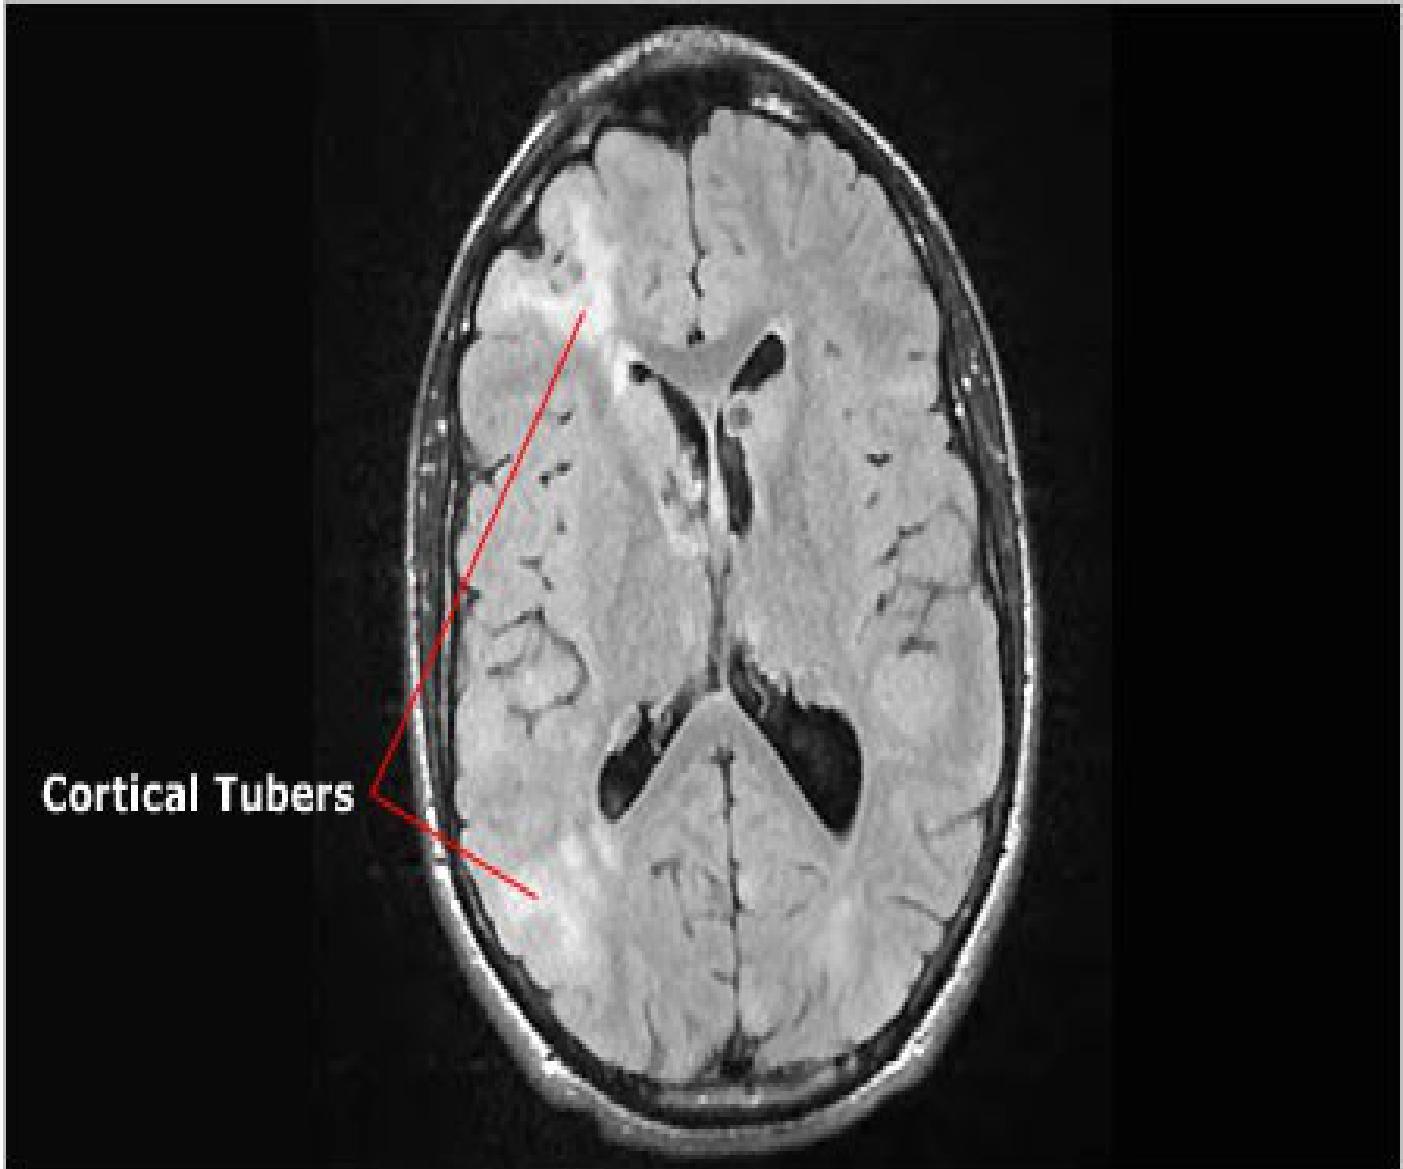

- Cortical Tubers: Brain lesions (Cortical dysplasias).

Cortical tubers:

- Cortical dysplasias (cortical tubers)